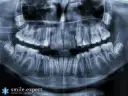

- Diagnostyka radiologiczna: Przed wszczepieniem implantu niezbędna jest precyzyjna diagnostyka. Najczęściej wykonuje się tomografię komputerową (CBCT), która pozwala dokładnie ocenić ilość i jakość kości oraz zaplanować umiejscowienie implantu. Koszt tomografii to od 150 zł do 400 zł.